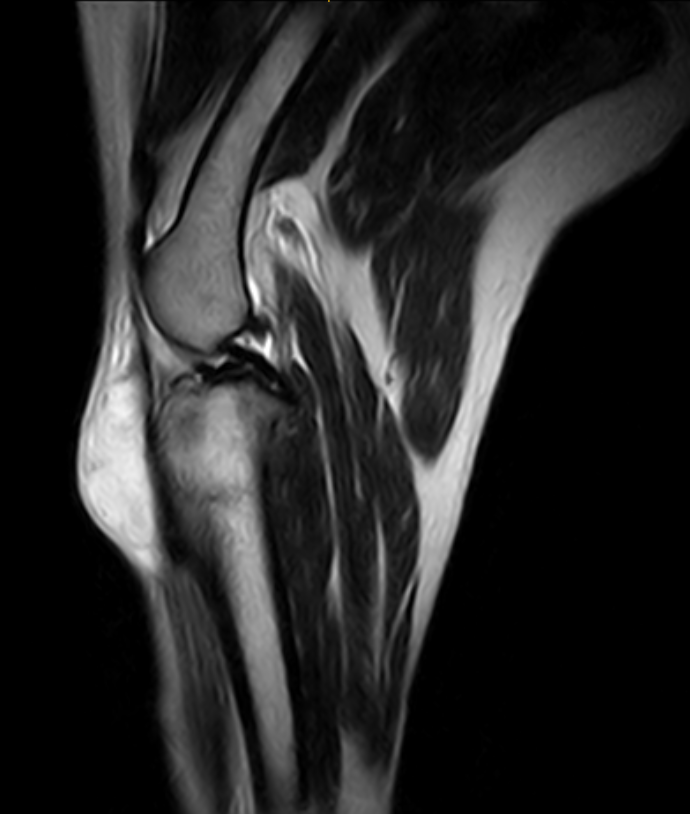

IMÁGENES CLÍNICAS

En la sección de imágenes clínicas, destacamos la precisión y claridad de nuestros estudios, respaldados por un equipo de radiólogos especializados en medicina veterinaria. Nos enorgullece ser un aliado confiable para veterinarios y clínicas, brindando un servicio rápido y eficiente para ayudar en la toma de decisiones clínicas fundamentadas.

Utilizamos resonancia magnética para obtener imágenes detalladas de tejidos blandos, articulaciones y el sistema nervioso central, permitiendo diagnósticos más precisos.